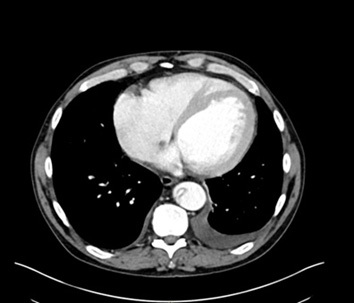

The gold standard for diagnosis is the computed tomography angiography (CTA) because of its speed, high sensitivity, and high specificity for aortic pathology. The sensitivity and specificity of CTA for acute aortic dissection approaches 100%.1,4,28-30 (See Figures 2-4.) An important point when ordering the CTA is to specifically state the reason, such as “possible aortic dissection,” so the correct CT imaging protocol will be done to maximize accuracy.

Figure 3. CTA Showing Intimal Flap in Dissection of the Descending Thoracic Aorta with Transverse View |

![]() |

Image courtesy of Daniel Migliaccio, MD |